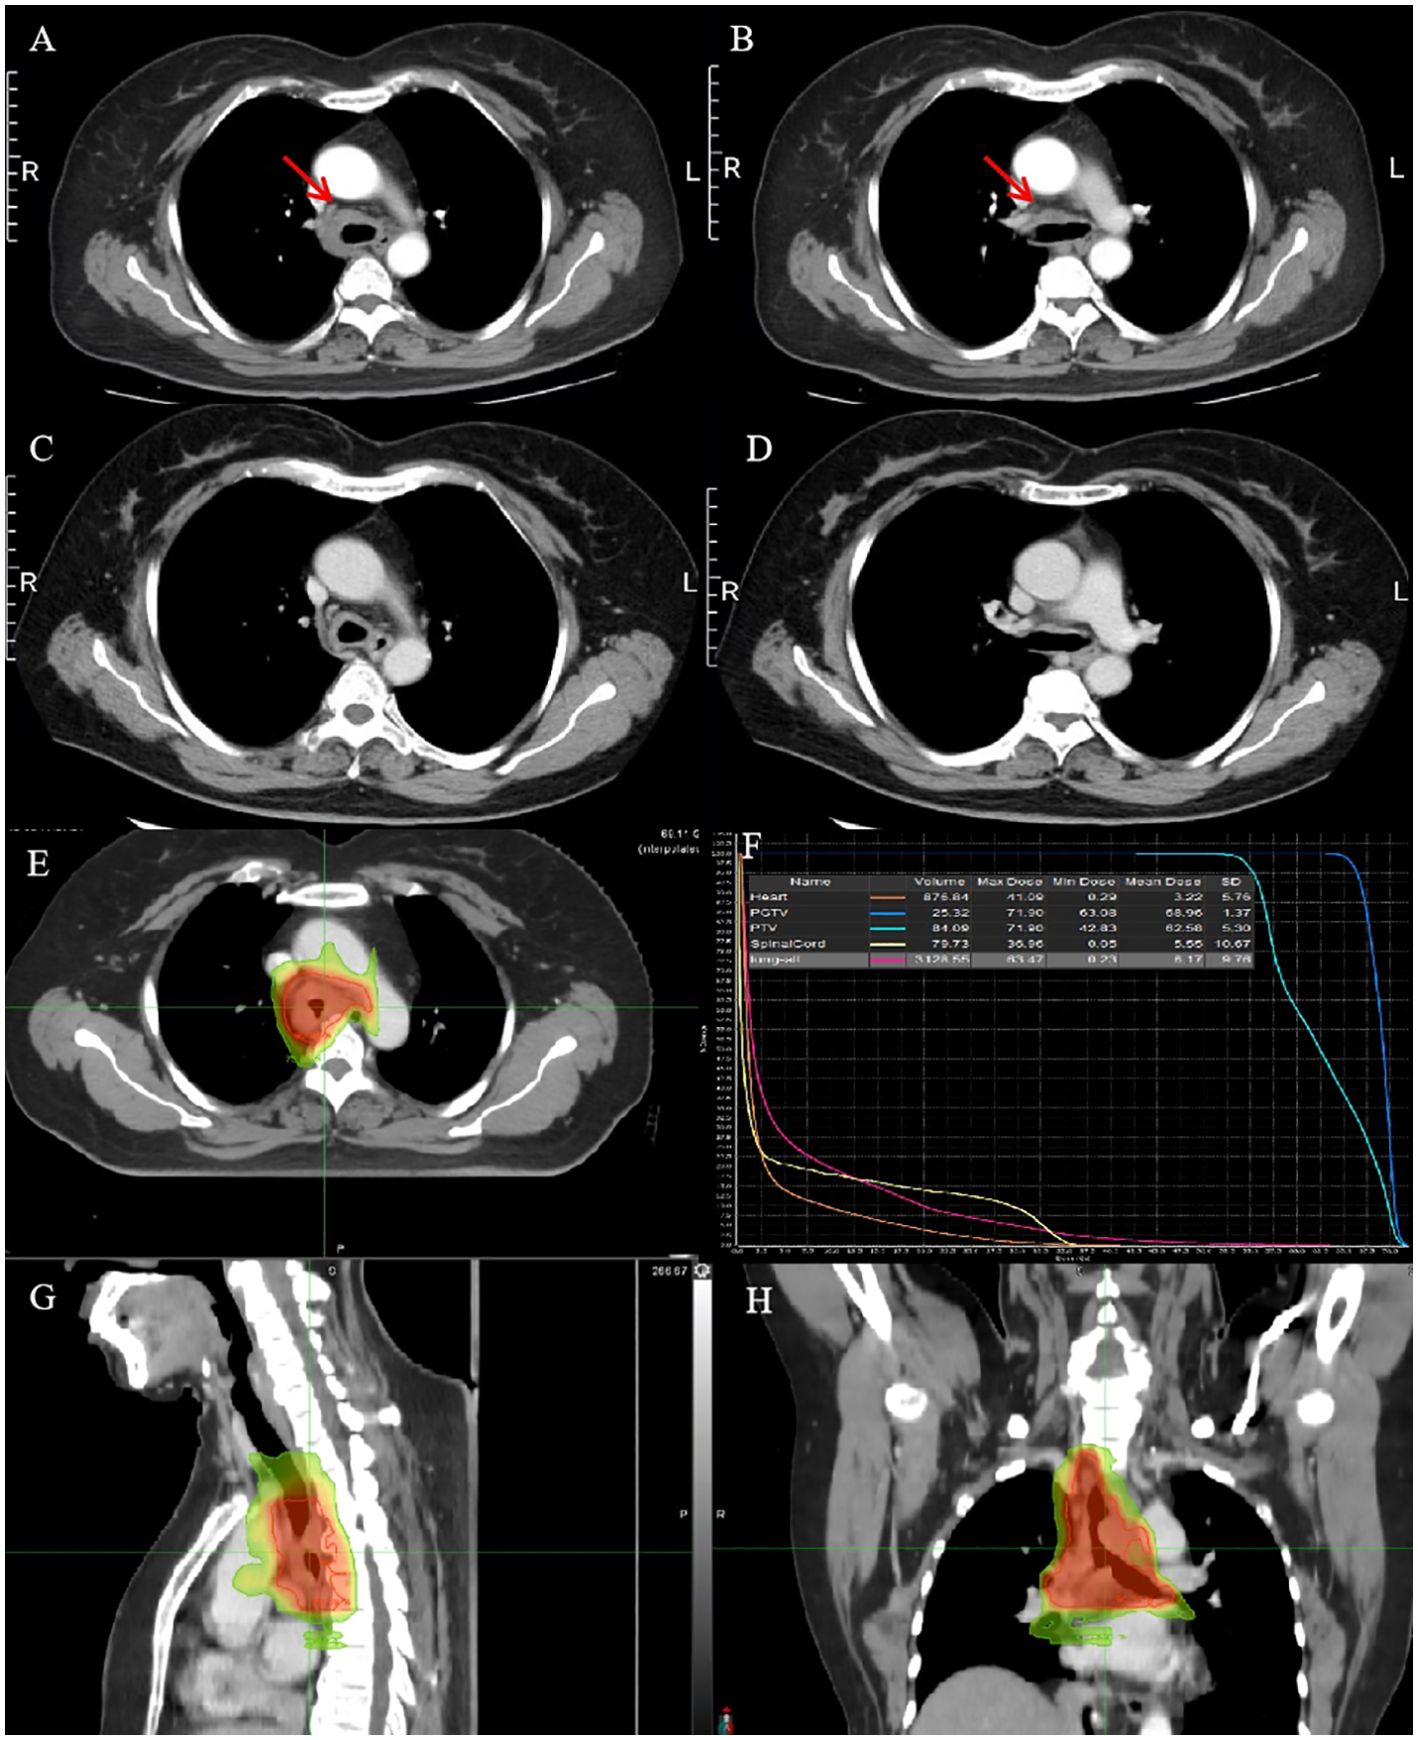

A 53-year-old woman presented with a history of more than 1 year of cough, coughing up phlegm, and shortness of breath for half a year, which worsened for half a month prior to her current presentation. Notably, she did not experience fever, thoracalgia, or any other relevant symptoms during that time. She denied any history of other diseases. The chest CT revealed the marked thickness of the lower segment and tracheal carina, leading to a locally narrowed trachea (Figures 3A, B). She had been hospitalized at local hospitals and received pharmaceutical treatment aimed at relieving her symptoms before her admission to our hospital. Regrettably, her shortness of breath did not yield with a significant relief. Subsequently, she was referred to our hospital for further medical assessment. After a whole-body examination was completed, there was no distant metastases found. The preliminary diagnosis pointed to an intratracheal mass. A fiberoptic bronchoscope verified a tracheal lesion situated 3 cm above the carina, and the lumen appeared notably narrow (Figures 4A–D). The pathological diagnosis of the biopsy was squamous epithelial high-grade intraepithelial lesion, with a tendency to be cancerous at the focal lesion. The tumor markers showed the following result: squamous cell carcinoma antigen at 2.74 ng/ml. The remaining examinations, as well as the laboratory examination, including routine blood, urine examinations, and those of the biochemistry examination, showed no abnormalities. The patient was diagnosed with tracheal SCC (cT4N1M0, stage IIIA) according to AJCC for lung cancer staging, but according to the classification proposed by Bhattacharyya, the stage was cT2N1M0, stage IIB. The surgery was difficult and risky, and radiation therapy was recommended. The patient received IMRT of true beam (Varian, USA). The target volume and radiation dose were as described in case 1 above combined with four cycles of chemotherapy of carboplatin plus paclitaxel (Figures 3E–H).

Figure 3. CT images and RT target of case 2 patient. (A, B) Computed tomography (CT) revealed a tracheal lesion. (C, D) The lesion was reduced at 1 month after RT. (E–H) RT target and DVH of case 2 patient; area of red line: 66 Gy; and area of yellow line: 54 Gy.

The patient had no obvious side effects during RT and recovered well. The CT result showed that the trachea lesion was markedly reduced at 1 month after RT (Figures 3C, D). She received four cycles of chemotherapy. At 6 months after RT, the chest CT still showed the thickness of the original tracheal lesion site, so a PET/CT was performed, which revealed the thickness of the tracheal carina and showed no 18-FDG uptake as well as without distant metastasis at nearly 9 months after RT (Figures 4E, F). Since then, she had undergone regular follow-up examinations every 3 months, and no symptom was reported. Her body movement though had returned to normal during the nearly 1-year telephonic follow-up. The patient provided written informed consent for the publication of the case details and the inclusion of accompanying images.